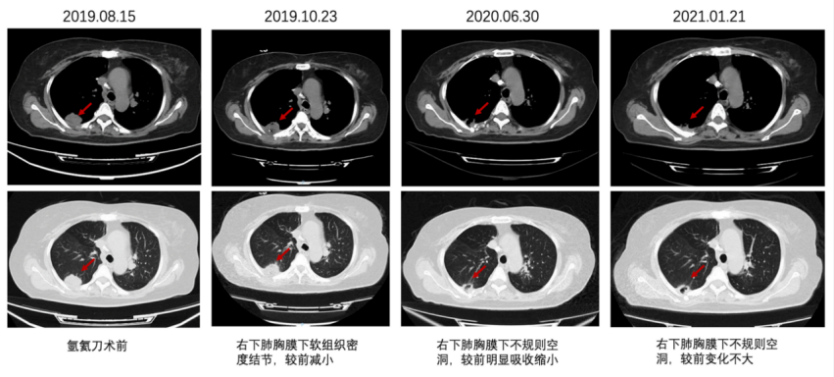

2014-2-25复查胸部CT示:右肺尖见不规则分叶状团块影,大小4.6cm×3.7cm,边缘见毛刺,局部胸膜粘连,考虑肿瘤性病变。2014-3至2014-5 行FOLFIRI方案化疗6周期。2014-8 复查胸部CT示右肺尖肿物较前略增大。2014-9-29 程志强教授于CT引导下行肺部病损氩氦刀手术。术后口服卡培他滨维持治疗,并口服中药治疗。(PFS 1年)

图1 CT引导下肺转移灶氩氦刀冷冻消融术

图3 右下肺胸膜下结节随访变化

图4 CT引导下右下肺胸膜转移瘤氩氦刀冷冻消融术

图5 氩氦刀术后规律口服瑞戈非尼,定期随访,疾病稳定